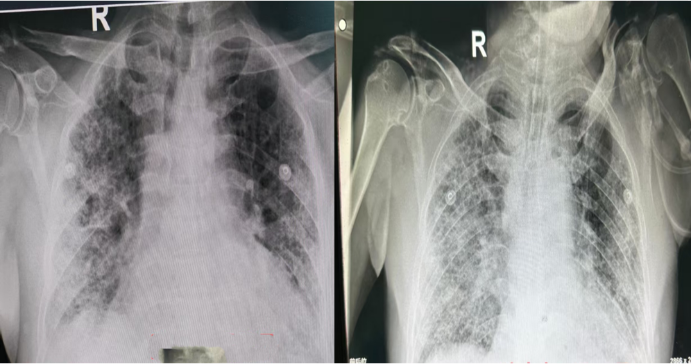

血气分析:pH 7.45,PaCO2 42 mmHg,PaO2 93 mmHg,FiO2 70%,P/F 133 mmHg,SaO2 98%复查胸片肺部感染,尤其右下肺实变影较前明显改善出现了新的问题——患者腹胀明显,腹部平片可见明显肠胀气(图4)

4  复查胸部X线片和腹部平片

患者住院第五天,呼吸机参数已进入相对平稳期。此时,患者的驱动压及平台压均处于安全范围(表4);复查胸片显示肺部情况较之前逐步好转(图6)

6  复查胸部X线片